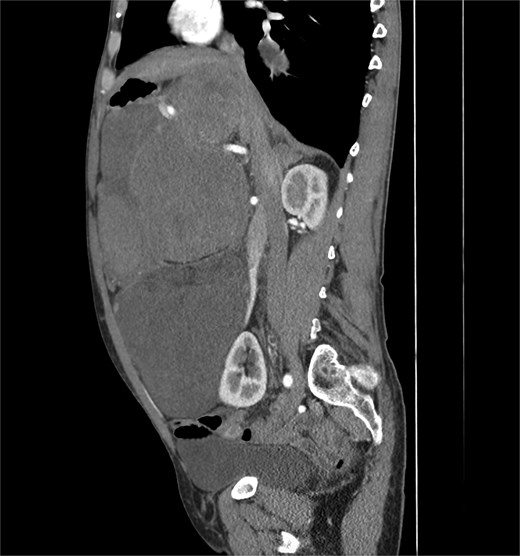

A 53-year-old man, ex-smoker and occasional alcohol consumer, reported several months of postprandial dyspepsia and increased bowel movements (3–4 per day), without weight loss or systemic symptoms. Physical examination revealed a distended, somewhat tense abdomen without focal tenderness. Laboratory tests, including complete blood count, biochemistry, and inflammatory markers, were within normal limits. Cross-sectional imaging demonstrated a multilobulated, predominantly solid retroperitoneal mass measuring 35 × 32 × 18 cm. Contrast-enhanced computed tomography (CT) and magnetic resonance imaging (MRI) showed displacement—but no frank invasion—of the inferior vena cava and aorta, encasement of mesenteric vessels, and compression of bowel loops. A notable anatomic variant was an ectopic left kidney located in the right paramedian pelvis. No distant lesions were identified (Figs 1 and 2). Three-dimensional CT angiography delineated the relationship with major vessels and aided operative planning (Fig. 3). After multidisciplinary discussion, primary surgical resection was favored given the well-circumscribed nature of the mass, the absence of metastatic disease, and the patient’s symptoms. Through a midline xipho-pubic laparotomy, a well-encapsulated, firm, tan-white mass occupying most of the retroperitoneal cavity was exposed. Sharp and blunt dissection allowed complete en bloc excision without capsular violation. Estimated blood loss was modest and no vascular reconstruction was required. Grossly, the specimen weighed approximately 12 kg and showed multinodular architecture with focal myxoid areas.

This case highlights diagnostic and management challenges posed by deep-seated fibroblastic tumors in the retroperitoneum. The retroperitoneum is a prototypical site for primary sarcomas, particularly well-DDLPS, leiomyosarcoma, and undifferentiated pleomorphic sarcoma; consequently, large masses are often presumed malignant [4]. DFH in deep sites can deviate from classic cutaneous presentations and display increased cellularity, myxoid change, and areas that simulate the dedifferentiated component of liposarcoma, complicating histologic interpretation [1–3]. The stakes of misdiagnosis are high: overcalling a benign lesion as sarcoma can prompt unnecessary systemic therapy or morbid surgery, whereas missing an aggressive sarcoma delays definitive treatment. Contemporary guidance underscores integrating morphology, immunohistochemistry, and, where indicated, molecular testing. MDM2 and CDK4 amplification assessed by FISH or immunohistochemistry supports a diagnosis of DDLPS; their absence, in the appropriate morphologic context, weighs against DDLPS [1, 2, 4]. CD34 expression in DFH is variable and nonspecific, whereas S100 highlights neural and adipocytic differentiation and tends to be negative in DFH [1, 2]. In our case, storiform/meningothelial-like architecture, low mitotic rate, negativity for S100 and SMA, and the clinicoradiologic appearance supported DFH. Imaging was informative: despite massive size, the lesion was well circumscribed and compressive rather than infiltrative, with major vessels displaced rather than invaded. From a surgical standpoint, the goal is complete macroscopic resection with an intact capsule and negative margins while preserving function, akin to principles used in retroperitoneal sarcoma surgery [4]. Preoperative three-dimensional vascular mapping aided planning and helped avoid vascular reconstruction. Given the benign biology, adjuvant radiotherapy or systemic therapy is not indicated after complete resection. Because deep-seated DFH may recur after incomplete excision, interval imaging (e.g. CT or MRI) in the first 2–3 years is reasonable, then symptom-driven thereafter, aligning follow-up with lesion size, location, and margin status. Recent reports continue to clarify the spectrum of DFH in unusual anatomical sites and reinforce the importance of targeted immunohistochemistry and, when necessary, molecular assays [1–3]. Advances in retroperitoneal sarcoma care emphasize how precise classification informs treatment selection and follow-up, underscoring the value of multidisciplinary review for large retroperitoneal masses [4, 5].